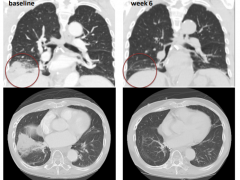

egfr20ins突变靶向药,JMT101+奥希替尼强强联合,肺癌耐药控病率95%

肺癌2026-01-08